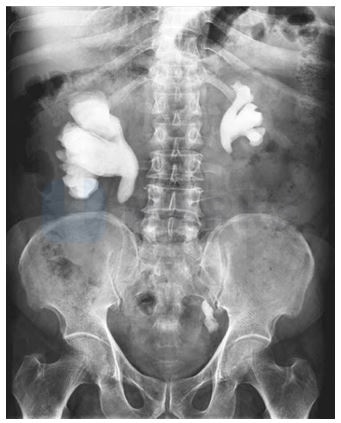

Observe the following X-Ray of the abdomen. What does it depict?

Deposition of calcium oxalate in kidney

Kidney stones or renal calculi are solid concretions or crystal aggregations formed in the kidney from dissolved urinary minerals. There are many types of kidney stones based on the crystals they are made up of. The most common calculi are made up of calcium oxalate (mulberry calculus). The second common calculi are made up of calcium phosphate (staghorn calculus). It is called so because of its shape. It takes the shape of the renal calyces and the pelvis. Rarely, struvite stones are produced by urea-splitting bacteria in people with urinary tract infections. Patients with certain metabolic abnormalities may produce uric acid stones (smooth and round calculus) or cystine stones. The condition of having calculi in the urinary tract is Urolithiasis. The condition of having calculi in the Kidney is Nephrolithiasis. Kidney stones cause severe pain in the abdomen & haematuria (blood in urine). Kidney stones can be treated by Lithotripsy (use of sound waves to break the stone) or surgery